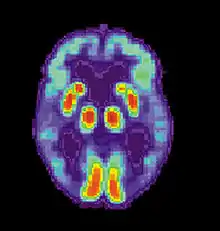

T. Awipi and L. Davachi sought to provide evidence of competing subregions in the medial temporal lobe (MTL) that differed on the type of content they encoded. The researchers conducted a study in which subjects were asked to perform an encoding task in a functional magnetic resonance imaging (FMRI) scanner, where they were presented with 192 full colour photographs of scenes (containing a centrally presented novel scene and a smaller image of one of six objects). Participants were also instructed to imagine using the presented object in each scene, and were asked to report whether they were successful. A memory test was administered after participants were removed from the scanner. The test consisted of all previously viewed scenes (old) and an equal number of novel scenes (new). They were asked to make an old/new judgement, and if the scene was responded as being old, they were asked to report it as being "remembered" or "familiar". They were then asked to pick an object that was paired with that scene. The researchers were trying to determine the levels of activation for source recollection for the objects paired with the scene during encoding.[18]

The researchers found that perirhinal cortex activation was greater for objects recalled, and parahippocampal cortex activation was greater when scenes were recalled.[18] The results provide evidence of distinct encoding activation in the subregions of the medial temporal lobe.[18] The first subregion is the perirhinal cortex, which encodes item information. The second subregion, the parahippocampal cortex, is involved in source information. The evidence provides support for the role of the right perirhinal cortex in attributing an object to the right source.[18] As decreased activation was associated with poorer performance, decreased activation of the right perirhinal cortex could be a possible mechanism for source confusion.